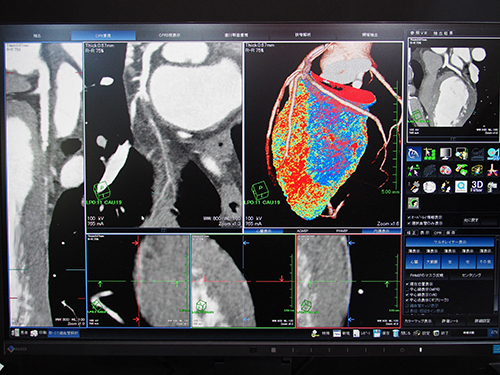

〈MRI:“4D Flow”(W.I.P.)〉

“4D Flow”(W.I.P.)は,初お披露目となった血流解析のソフトウェア。MRIの3D phase contrast法にて得られるデータを解析し,x軸,y軸,z軸方向の信号強度をベクトル化することで,血流の方向と速さの可視化を実現する。血流の方向が矢印で,流速がカラーマップで示され,血流がよどんでいるところ,乱流しているところを観察できる。現在,症例検討を重ねているところで研究レベルではあるが,腹部大動脈瘤や脳動脈瘤の評価,大動脈解離の予測に利用できる可能性があるという。また,先天性心奇形は症状がなければ手術を控えるが,4D Flowにより心血流を把握することで,手術が必要なタイミングを適切に判断できる可能性があると期待される。2015年中のリリースを目標に開発が進んでいる。

血流の方向と速さの可視化した“4D Flow”(W.I.P.)